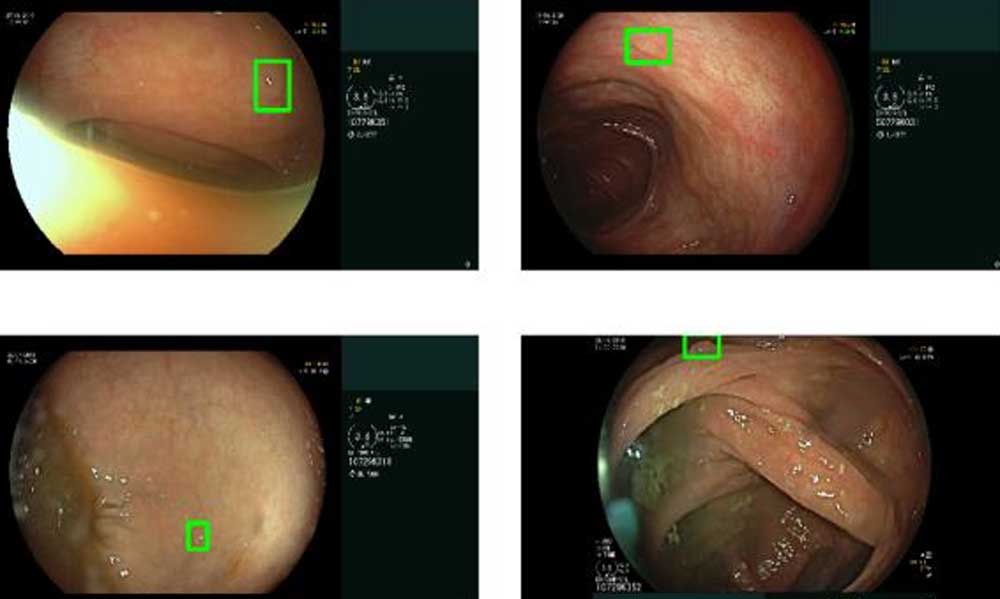

Das Standardverfahren für die Erkennung und Entfernung von Polypen ist die Darmspiegelung, bei der ein Gastroenterologe den Darm über eine Kamerasonde nach präkanzerösen Polypen untersucht.

In einer neuen Forschungsarbeit stellen Google-Forscher nun eine Bildanalyse-KI vor, die die Kamerabilder während der Darmspiegelung analysiert und Gastroenterologen hilft, Polypen zu identifizieren.

Das zweite KI-System sucht direkt in den Aufnahmen nach Polypen. Die Forscher haben die Bildanalyse-KI dafür mit Aufnahmen von 3.600 Untersuchungen oder 86 Millionen Bildern trainiert und anhand von Aufnahmen von 1.400 Untersuchungen getestet.

In den Tests erkannte DEEP (Detection of Elusive Polyps) 97 Prozent aller Polypen, darunter solche, die in den Testdaten von mehreren menschlichen Experten nicht erkannt worden waren. Waren die Polypen nur kurz im Bild zu sehen, erkannte DEEP noch 88,5 Prozent bei fünf Sekunden und 84,9 Prozent bei zwei Sekunden Sichtbarkeit.

Eine erste klinische Überprüfung fand in Kooperation mit dem Shaare Zedek Medical Center in Jerusalem statt: Dort unterstützte DEEP Gastroenterologen bei 100 Darmspiegelungen. Laut Google half das System im Schnitt, ein Polyp pro Untersuchung aufzudecken, der andernfalls unbemerkt geblieben wäre.

DEEP verfehlte darüber hinaus keinen Polypen, der menschlichen Experten ebenfalls auffiel und meldete nur 3,8 falsche Alarme pro Untersuchung. Laut der Forscher war das Feedback der Gastroenterologen durchgängig positiv. Weitere Kooperationen sollen folgen, um die Forschungsergebnisse zu validieren.